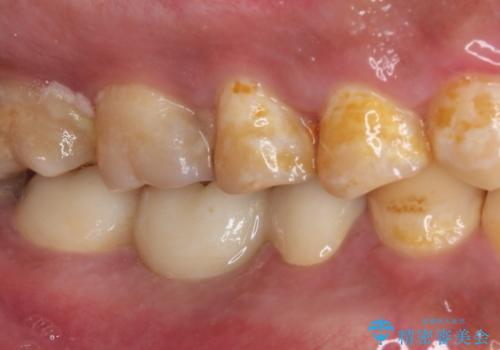

神経を取り除く可能性のあった奥歯ですが、何とか保存することができました。

奥歯はしっかりと治療することができたので、今後は虫歯予防と他の要治療歯の処置を行っていくことになります。